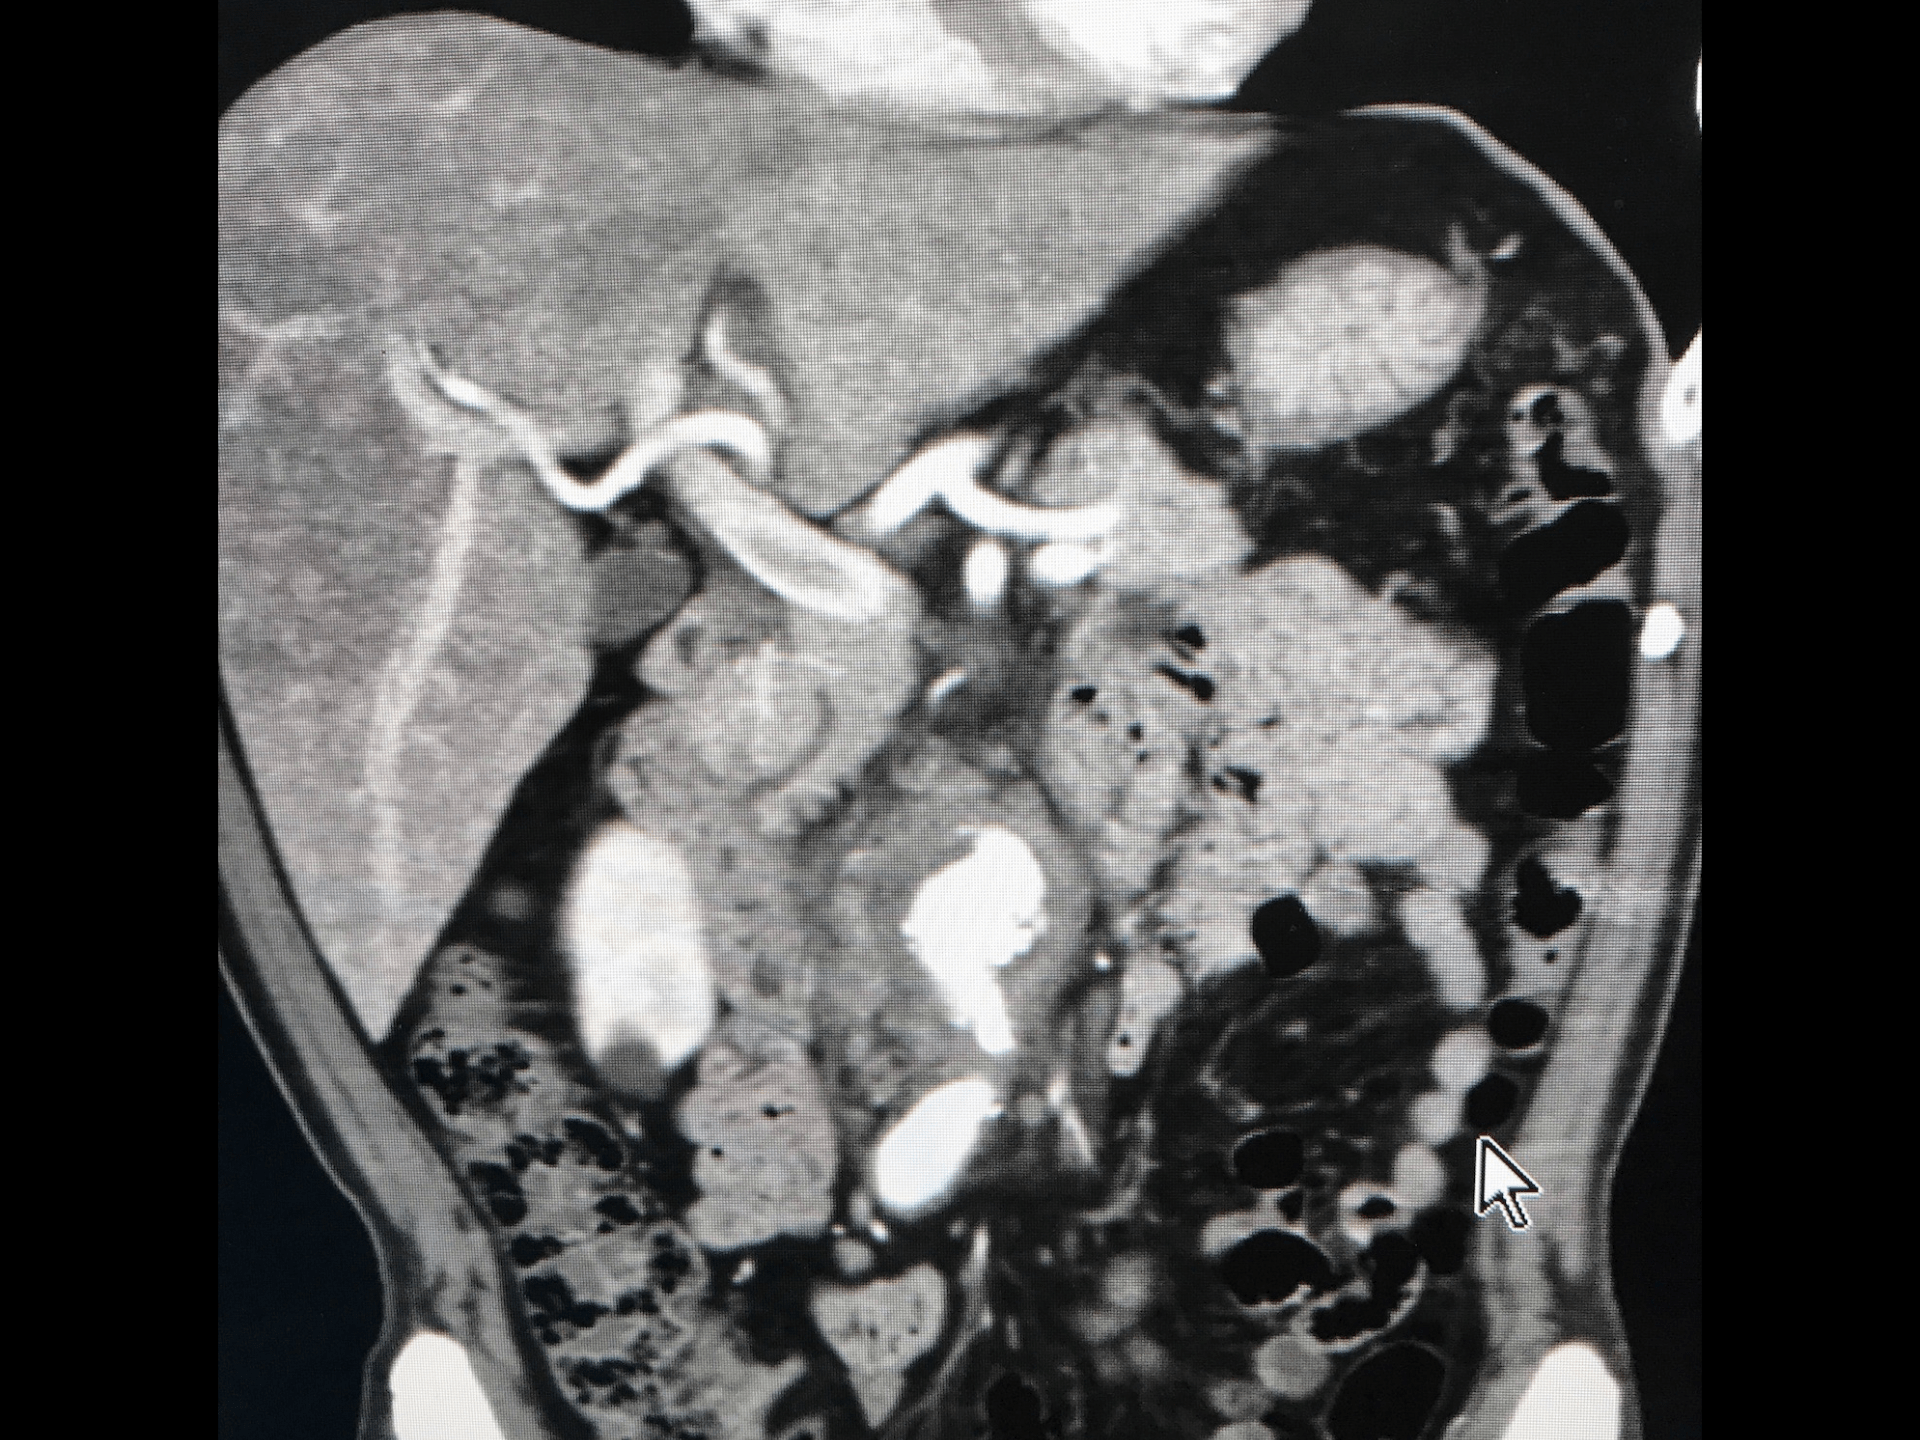

炎症性大動脈瘤(IAAA) 1972年にWalkerらが提唱した概念 Br J Surg 1972; 59:609-614. 腹部大動脈瘤の 5-10 % をしめる Ann Surg 1997; 225: 155-164 厚い動脈瘤壁(1cm以上 J Vasc Surg. 1985;2(6):859 広範な動脈瘤周囲と後腹膜の繊維化 隣接する腹部臓器との癒着 An article from the E-Journal of the ESC Council for Cardiology Practic e ) Vol.7,N°10 - 18 Nov 2008

#7.

炎症性大動脈瘤(IAAA) ①腹痛/背部痛②体重減少③ESR/CRPの上昇 機序は“In ammatory variant”と推定されている 65-90%が有症状(アテローム性は8-18% 25%が拍動性 53%が尿管圧迫 (18-21% 慢性腎障害 術前診断は13-33% An article from the E-Journal of the ESC Council for Cardiology Practic ) e ) fl Vol.7,N°10 - 18 Nov 2008

画像診断における炎症性大動脈瘤の評価